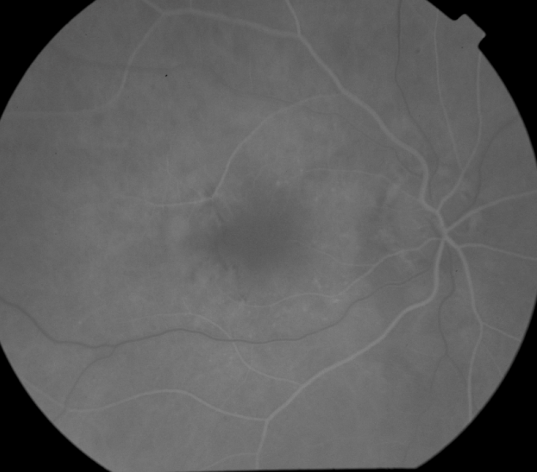

ANGIOGRAM INTERPRETATION |

FUNDUS DESCRIPTION: |

OD Red-Free: Pre-Injection: Arterial: A-V: Venous: Recirculation: Late:

OS Red-Free: Venous: Recirc: Late:

Impression

Plan |